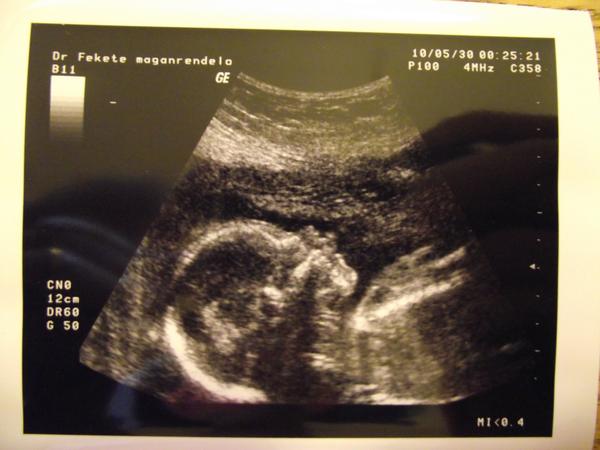

Bre ranko zienky - pre mna je to najkrajsie ranko, nakolko vcerajsie detailne morfologicke sono dopadlo na jednotku 🙂 🙂 🙂 🙂 🙂 🙂 🙂 🙂 🙂 🙂 Vsetko je v poriadku, vsetky organiky su v poriadku, srdiecko bije ako zvon - videla som 4komory s chlopnami ako sa otvarali a zatvarali 🙂 , vazime 419g, dlzka sa nedala zmerat pretoze robilo sustavne kotrmelce, mame zdravy zaludocek, oblicky, mechurik, plucka, chrbticku, vsetky prstiky, atd, a mame aj pindurika 😀 😀 😀 😀 Je to 100% chlapciatko - ako vyslo podla vypoctu krvy partnerov aj cinskeho kalendara - mimochodom 😀 😀 😀 takze @franica moja, bude to predsa len ten Georginko Clooney 😀 😀 😉

Inac placentu mam polozenu vzadu - co je super, krcok uplne zatvoreny, poloha Georginka je zatial pozdlzna - este sa neusalasil hlavickou nadol, hlavne ze tam robil nonstop kotrmelce 😀 😉